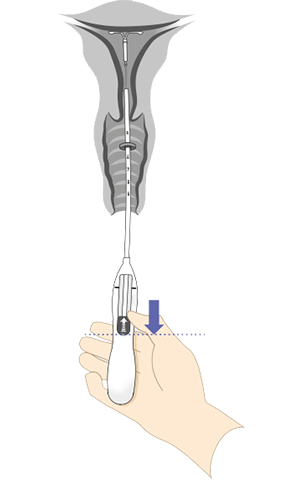

Énhånds innføring med Bayer-innføringssystem

Det integrerte innføringssystemet gjør det mulig for deg som lege, jordmor eller helsesykepleier å klargjøre innlegget med én hånd. Innføringshylsens diameter er 3,8 mm

Innføringssystemet har ergonomisk formet glideknapp og håndtak

8 trinn for riktig plassering av Kyleena